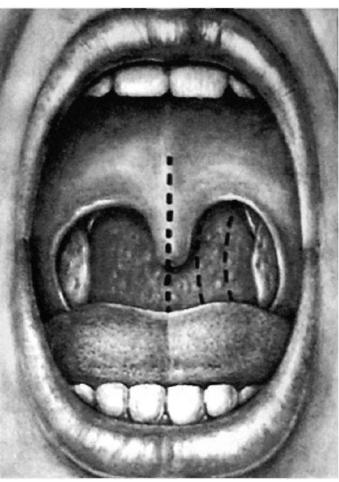

Рентгенография небного шва: Медицинские исследования и диагностика